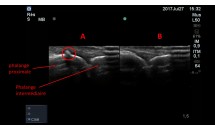

Les lésions de l'extenseur digital, en regard de l'articulation interphalangienne distale, entraînent une déformation en flexion de la dernière phalange des doigts longs liée à la section (ou à la...